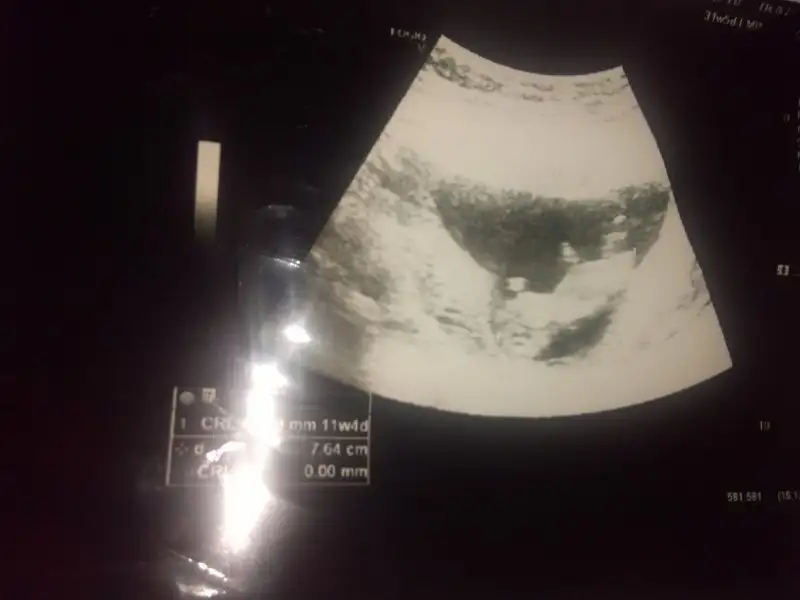

Cnm geç kaldım bıraz siteye giremedim simsi girdim hem 11+4 hemde 12+4 paylaşıyorum bir bak sana zahmet en son resim 11+1 di sanırım12+ canim